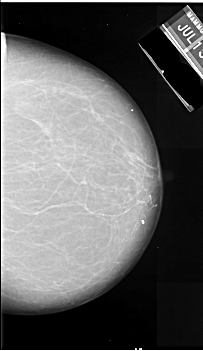

A_1090_1.RIGHT_CC

RIGHT_CC LINES 6301 PIXELS_PER_LINE 3646 BITS_PER_PIXEL 16 RESOLUTION 42 NON_OVERLAY